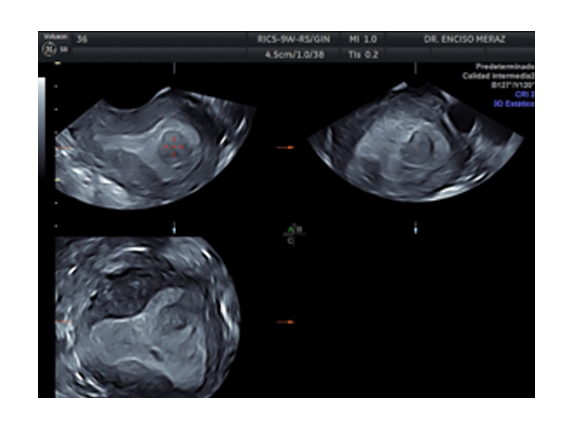

MIOMATOSIS

Leiomiomatosis, son los tumores benignos uterinos mas frecuentes de la mujer.

Se originan de las celulas musculares del utero. Tienen una frecuencia del 30% de todas las mujeres, estando con mayor frecuencia en la decada de los 30 y 40 años.